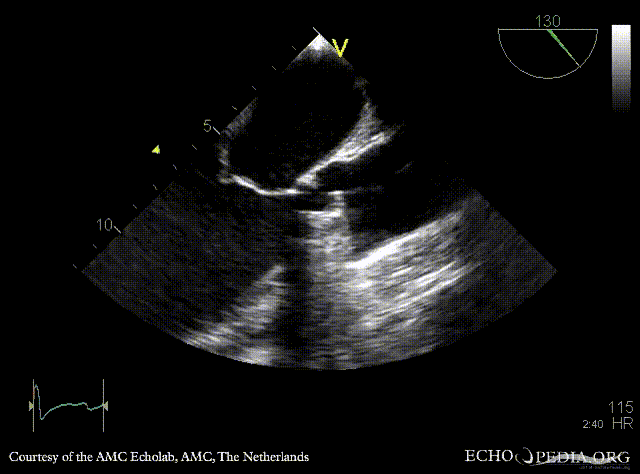

Thrombus of prosthetic aortic valve

TEE: thrombus of prosthetic aortic valve TEE: severe aortic regirgitation